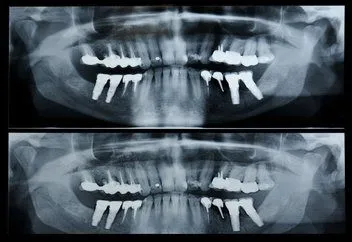

A panorex is a very impressive piece of imaging machinery in that it is

capable of identifying many issues and structures that a normal x-ray is not.

Initially you will sit in a chair with your chin on a small ledge. Once

positioned in the machine, it will rotate around your entire head taking a

full 360 degree view of the teeth, head, sinuses and bones.

The

ability to view the full structure of your head as a whole is very informative

to the dentist. It will allow us to see any potential problems and make sure

that everything is functioning as it should be. The panorex is capable of

viewing specific types of structural problems, infections or asymmetry among

many others.